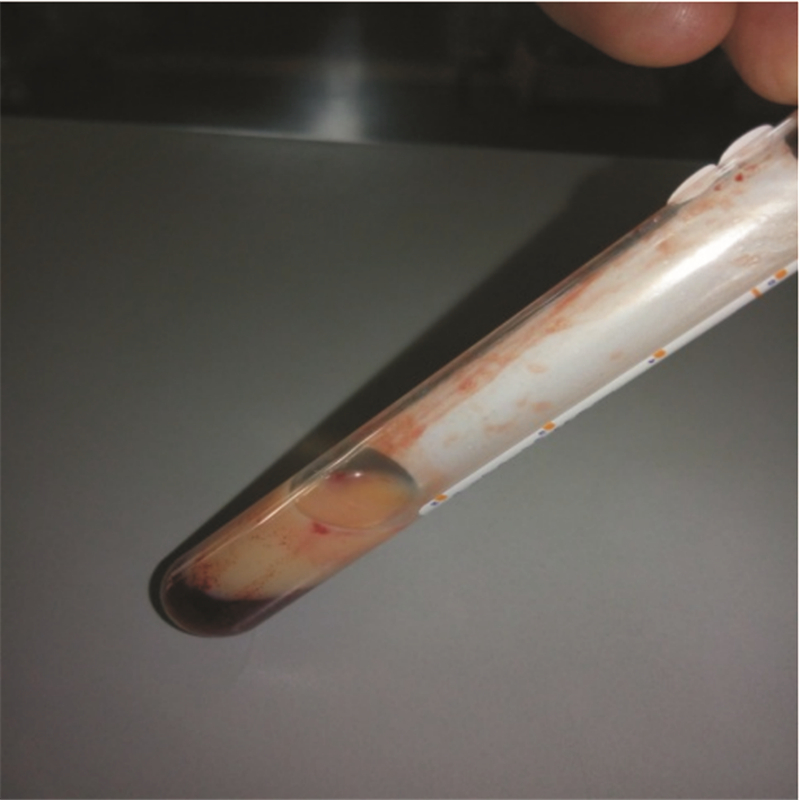

患者于入院10 h前进食后突发上腹部疼痛,呈持续性刀割样剧痛,伴腹胀,恶心、呕吐,呕吐物为胃内容物,无呕血、黑便,无腰背放射痛,无发热、寒战。在当地医院就诊,查血淀粉酶348 U/L,尿淀粉酶4 082 U/L,腹部CT示:“胰腺周围渗液,水肿,腹腔少量积液”(图 1),诊断考虑“急性胰腺炎”。入院查体患者痛苦貌,双肺呼吸音粗,可闻及干湿性啰音及散在湿啰音。窦性心动过速,心率101次/min,心律规整,各瓣膜听诊区未闻及病理性杂音。腹部膨隆,未见胃肠型。腹壁张力大,压痛明显,宫底触诊不清,胎心140次/min,宫缩不规律。肠鸣音减低。2014年5月12日抽血化验时发现患者严重脂血(图 2),积极给予患者抑制胰液分泌、抑酸、支持等对症支持治疗。诊断考虑高甘油三酯血症急性胰腺炎(HTGP),同时给予特异性治疗:低分子肝素钙4 100 U皮下注射 q12 h,非诺贝特 0.1 口服q8 h。

| 图 2 患者2014年5月11日抽取血样 |